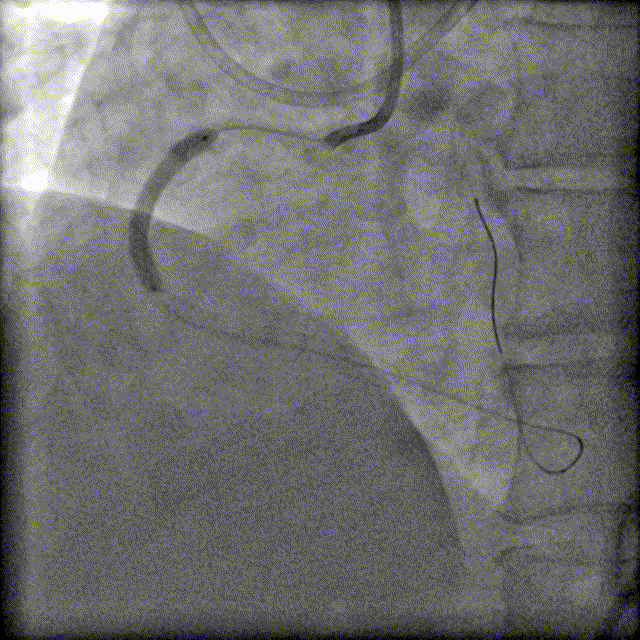

LM未见异常,LAD原支架内血流通畅,支架近端可见局限性偏心狭窄90%,中远段未见狭窄或闭塞,前向血流TIMI-3级;中间支近中段弥漫性狭窄50%-60%。

RCA原支架内100%闭塞,前向血流TIMI-0级;可见LAD向RCA发出侧支,侧支血流1级。